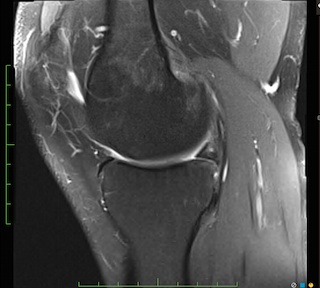

Figure 2 for case Meniscal ossicle

Figure 2